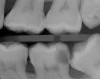

These findings demonstrate that the pulpal diagnostic term asymptomatic irreversible pulpitis needs to be updated. This diagnosis represents a tooth that presents with clinical and radiographic evidence of caries (Figure 2) and responds normally to clinical sensibility testing to cold. The AAE Consensus Conference Recommended Diagnostic Terminology defines asymptomatic irreversible pulpitis as "a clinical diagnosis based on subjective and objective findings indicating that the vital inflamed pulp is incapable of healing. Additional descriptors: no clinical symptoms but inflammation produced by caries, caries excavation, trauma."12 In reality, this diagnosis can technically only be confirmed histologically. But, according to the results of the study conducted by Ricucci and colleagues13, teeth that responded normally to cold testing demonstrated only a mild to moderate accumulation of chronic inflammatory cells beneath the tubules that were affected by caries, and the inflammation did not extend through the entire portion of the pulpal tissue. Therefore, the pulp of a carious tooth that responds normally to cold testing should be diagnosed as normal pulp, not asymptomatic irreversible pulpitis. A more pertinent use of the diagnostic term asymptomatic irreversible pulpitis would be for cases involving a pulp polyp or internal resorption of a vital tooth (Figure 3).

(2.) Bitewing radiograph of tooth No. 18 with radiographic evidence of distal carious defect. This tooth tested within normal limits to cold sensibility tests. Under the current diagnostic terms, the pretreatment pulpal diagnosis would be asymptomatic irreversible pulpitis.

Figure 2